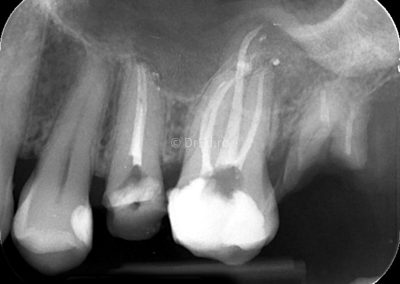

Galerie

Toate imaginile, fotografiile și radiografiile publicate pe acest site sunt protejate prin drepturi de autor și constituie proprietatea exclusivă a Dred.ro.

Aceste materiale sunt furnizate exclusiv în scop informativ și educațional și nu conțin date cu caracter personal sau informații care permit identificarea pacienților, în concordanță cu legislația privind protecția datelor cu caracter personal și GDPR.

Reproducerea, copierea, distribuirea, publicarea, transmiterea, modificarea sau orice altă utilizare, integrală ori parțială, a acestor materiale, în orice formă și prin orice mijloace, fără consimțământul prealabil scris al titularului drepturilor, este strict interzisă și poate atrage răspunderea civilă și/sau penală, în condițiile legii aplicabile privind drepturile de autor și protecția proprietății intelectuale.